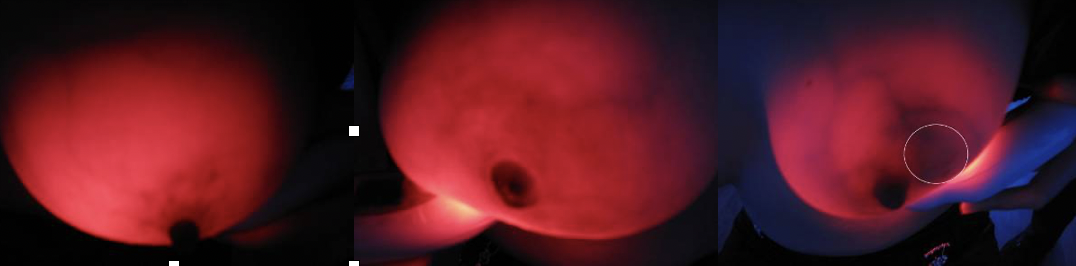

The accuracy of mammography as a breast cancer screening method will be evaluated in the future.However, breast fluoroscopy (TBS) is highly dependent on the experience and skills of the operator, and the judgment criteria and demonstration images for various breast diseases have not been unified yet, which may affect the evaluation results of future trials.To this end, the preliminary experiment was carried out to review TBS of clearly diagnosed benign and malignant breast diseases and normal women, summarize the imaging characteristics of various types of breast and obtain typical TBS images, which will be used for TBS training in the future and guide the development of the next evaluation test.

Step 4: Fill in the Evaluation Form of Breast Optical Detector Examination (TBS), and record the TBS imaging characteristics of various breast diseases from the aspects of overall breast transmittance, mass shadow, vascular shadow and the relationship between them.

(4) Examination method: The examiner holds the mammary diptometer in his left hand, and the light source is close to the lower part of the breast. The breast is held up and the intensity of the light source is adjusted, and the four parts of the areola, the inner side of the breast, the outer side of the breast and the armpit are observed in order.